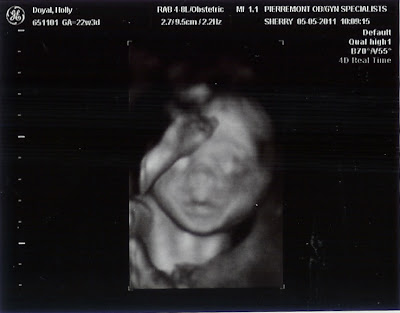

Thursday, May 5, 2011

Another Day, Another Doctor's Appointment

Another day, another doctor's appointment. That's the story of my life right now!

But today came with mostly good news, which was a very welcome change! I guess the good part of having so many appointments/ultrasounds is that you get to see your baby more. I could already fill up an entire scrapbook with just ultrasound pics! Max looked so cute and gave me some good profile and head shots- he's still a little alien looking, but I think he's adorable! And everything seems to be right on track with him.

I'm slowly coming around too. Patty the Placenta (thank you Anne for naming my body parts!) has moved her way up to the top of my uterus, so no more fears of placenta previa/accreta. I do have an umbilical hernia (which is very evident if you've seen me and my belly button that arrives 5 minutes before the rest of me!) that will have to be surgically repaired at the time of my C-section. I also was told to "take it easy" since I have started to have a lot of frequent Braxton Hicks contractions. Yeah, right- tell that to my 3 year old!!!

It's been a really eventful month to watch and feel Max moving around. David can now feel him and (if we're patient) we can spend endless amounts of time watching my belly move as Max gets his groove on in there!

So, here's the good stuff: some pics from today's ultrasound. Max was (as always) very wiggly, but cooperated enough to get some good shots.